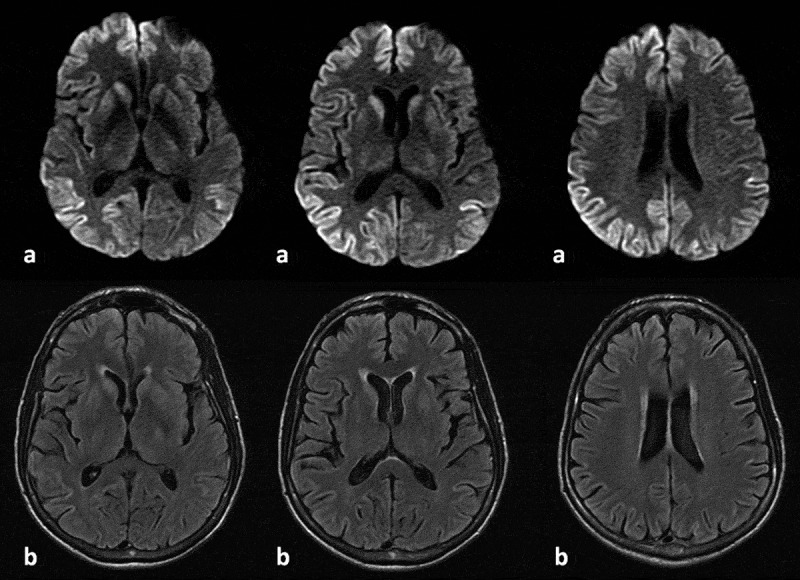

We describe a case of probable sporadic Creutzfeldt-Jakob disease in the setting of well-controlled HIV and discuss whether exist, in fact, HIV-related factors that may predispose to the development of prion disease. To the best of our knowledge, this is the third report of this association.